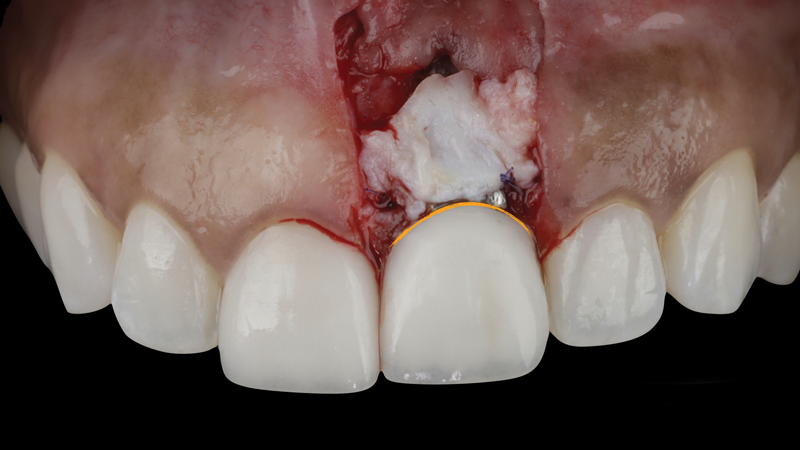

(5.) After the abutment and crown were recontoured, a soft-tissue graft was taken from the patient’s tuberosity and secured over the implant to add supracrestal volume, and the restoration was replaced. Note the planned position of the margin indicated in orange.

Figure 5

(6.) After the abutment and crown were recontoured, a soft-tissue graft was taken from the patient’s tuberosity and secured over the implant to add supracrestal volume, and the restoration was replaced. Note the planned position of the margin indicated in orange.

Figure 6

(7.) After the abutment and crown were recontoured, a soft-tissue graft was taken from the patient’s tuberosity and secured over the implant to add supracrestal volume, and the restoration was replaced. Note the planned position of the margin indicated in orange.

Figure 7